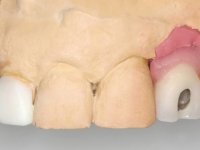

Paciente do sexo feminino, com 47 anos não fumadora. Apresentou-se na consulta com o dente 1.3 com tratamento endodôntico e com um espigão falso coto fundido, reabilitado com uma coroa provisória. Os dois incisivos laterais superiores são conoides e de reduzida dimensão. O dente 2.2 apresenta mobilidade, consentânea com uma significativa reabsorção óssea entre o dente 2.1 e o dente 2.3 Os dois incisivos centrais estão separados por um diastema de 3mm e o dente 2.3 apresenta uma oclusão cruzada com o dente antagonista. Verifica-se também a ausência de alguns dentes posteriores e uma higiene oral razoável. Na segunda intervenção realizada passados 8 anos, verificou-se que os incisivos centrais superiores se apresentavam cromaticamente mais escuros e apresentavam um sulco longitudinal no esmalte que estando pigmentado comprometia esteticamente o sorriso. O trabalho realizado na primeira fase do tratamento mostrava-se competente estética e funcionalmente. Por fim, um ano após a última intervenção, a paciente apresentou-se com uma fratura da faceta colocada no dente 2.1 provavelmente em resultado de estar em contacto com o coto do implante. A rigidez da anquilose implantar, pode ter sido a causa desta fratura. Outros casos deste tipo de fratura já foram observados por mim em situações clínicas idênticas. A faceta do dente 1.2 apresentava-se esteticamente comprometida e a própria estrutura dentária apresentava uma pequena cárie e, pelo que se recomendaria a sua substituição.

O tratamento iniciou-se com a re -preparação do coto do espigão falso coto fundido, com o objetivo de colocar as linhas de acabamento cervical com uma localização intra-sulcular e simultaneamente confecionar uma coroa provisória adaptada. Com um tratamento ortodôntico muito simples, fechou-se o diastema entre os incisivos centrais superiores e estabilizou-se esta posição com um arame colocado na superfície palatina dos centrais, funcionando como contenção. Posteriormente procurou-se fazer uma tração ortodôntica lenta do dente 2.2 com o intuito de diminuir, ainda que muito ligeiramente a perda óssea vertical nessa zona. Finalizada a tração, foi feita a extração do dente 2.2 e a zona foi reabilitada provisoriamente com uma coroa de resina composta colada aos dentes adjacentes. Foi colocado um implante dentário na zona do dente 2.2 sendo novamente colada a coroa provisória em resina, reabilitando provisoriamente a paciente durante o período de osseointegração. No dente 1.3 foi feita uma gengivectomia com bisturi elétrico, com a intenção de subir o nível cervical do 1.3 conseguindo uma maior harmonia com o dente 2.3. Estabilizados os tecidos moles, foi feita uma impressão com a técnica de moldeira aberta, utilizando silicones de adição de consistência “putty” e “light”. A recolha da cor, tanto da componente dentária como dos tecidos moles foi feita pelo ceramista no consultório.  No laboratório as impressões foram passadas a gesso e deram origem a modelos de trabalho que foram devidamente analisados. Foi decidido confecionar um “abutment” metalo-cerâmico aparafusado sobre o implante. Este “abutment” foi fundido com uma liga nobre e posteriormente revestido a cerâmica coronária e gengival. Dada a inclinação do implante o aparafusamento condicionou de forma inevitável a saída do orifício do parafuso pela superfície vestibular. No sentido de esconder esta situação, o desenho do “abutment” já foi idealizado com a intenção de acomodar na superfície vestibular a colagem de uma faceta feldspática. Este “abutment” foi provado em boca e foram feitos ajustes no componente cerâmico gengival. A sua adaptação aos tecidos moles foi feita tanto de forma subtrativa, com broca, como de forma aditiva, acrescentando resina composta de tonalidade gengival. Este acrescento de resina seria orientador do ceramista na colocação final da cerâmica de tonalidade gengival. A coroa que reabilitaria o dente 1.3 foi cimentada nesta consulta de prova com cimento de ionómero de vidro reforçado com resina composta. Finalizado o trabalho em laboratório da faceta sobre o 1.2 e o “abutment” e a faceta para o implante este foi colado em boca, após a colocação do isolamento absoluto. O trabalho satisfez plenamente a paciente. Durante oito anos a paciente foi seguida regularmente, mostrando-se agradada com o tratamento efetuado, no entanto começou a mostrar interesse em intervir esteticamente nos incisivos centrais superiores. Decidida a segunda fase da nossa intervenção, foi feita a preparação dentária dos dentes 1.1 e 2.1 para a colocação de duas facetas feldspáticas. Particular cuidado foi tido na preparação inter-proximal distal junto ao “abutment” do implante. Foi preciso avaliar muito pormenorizadamente o eixo de inserção da faceta em relação ao “abutment”. As facetas feldspáticas foram confecionadas em laboratório e posteriormente coladas em boca após a colocação de isolamento absoluto. Um ano após, iniciamos a nossa terceira fase de tratamento, após a faceta colada no dente 2.1 ter fraturado. A preparação dentária foi feita sobre a faceta colada, procurando estender mais para palatino o interface inter-proximal distal. O objetivo seria passar para mais palatino do ponto de contacto o interface faceta-dente. O preparo dentário do dente 1.2 também foi muito reduzido, limitando-se a criar um eixo de inserção. Após confecionadas a coroa total e a faceta em laboratório foram coladas em boca. Primeiro foi colada a coroa utilizando-se um isolamento relativo com teflon, posteriormente foi colada a faceta após a colocação do isolamento absoluto. Na coroa utilizei este tipo de isolamento para evitar a utilização de grampos. Seria difícil de aplicar pela forma e dimensão do dente e agressivo para os tecidos moles. Após a colagem foi avaliada a integração oclusal do trabalho.